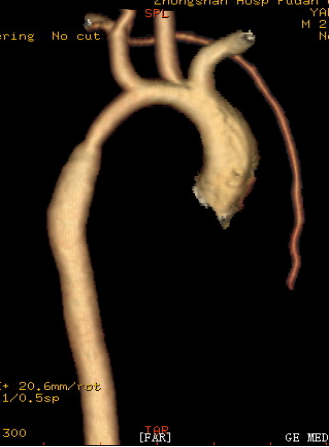

4、多排螺旋CT三维成像 (Multi - slice CT Three - dimensioned Angiography ):

大血管形态、 冠状动脉形态-依靠心率

主动脉弓缩窄伴弓部及降部发育不良 主动脉弓离断:升主动脉与降主动脉不连续,

降主动脉通过粗大动脉导管供血